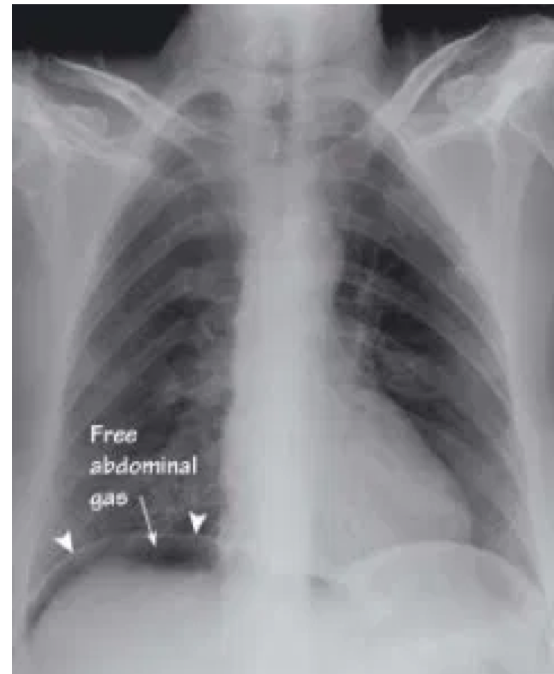

what imaging is needed to investigate peritonitis?

Erect CXR (check for air under the diaphragm)